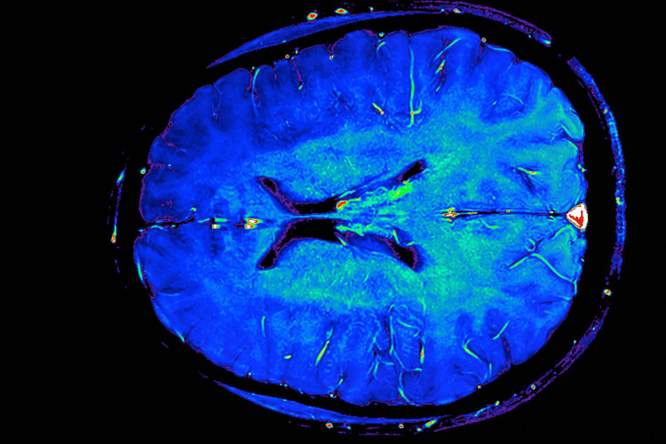

Hersenscans sporen alzheimer op

De hersenscans kunnen vaststellen met welke vorm van geheugenverlies de patiënt kampt. Met een specifiekere diagnose weten patiënten beter hoe hun toekomst eruitziet.